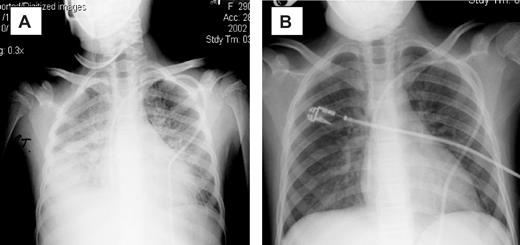

The introduction of etanercept was associated with a reduction in oxygen requirement in 13 patients, and in 10 patients a complete response (CR) to therapy was achieved (Table 2). Clearing of radiographic infiltrates accompanied clinical responses (Figure 1). The median time to CR was 7 days (range, 3-17 days), with a median of 2 etanercept doses (mean, 3 doses; range, 1-5 doses) required to achieve a CR. Two patients achieved CR after the first dose, and 4 achieved CR after the second dose of etanercept. Three of 8 (38%) patients on mechanical ventilation at initiation of etanercept therapy achieved a CR. Patients were more likely to have a CR if etanercept was started early after the onset of clinical IPS symptoms. For the 10 responding patients, therapy was initiated a median of 1 day from the diagnosis of IPS, compared with a median of 3 days in the 5 treatment failures. Although small numbers preclude statistical analysis, the 5 patients who did not achieve CR had a longer duration of severe symptoms (4 of 5 were mechanically ventilated ≥ 48 hours) at study entry.

Chest radiographs of patient 5. (A) Before therapy. (B) On therapy. Panel A was obtained on day 0 of study, with the patient requiring 100% FiO2 via bilevel positive airway pressure (BiPAP). Panel B was obtained 3 days later, with the patient now off all supplemental oxygen support.